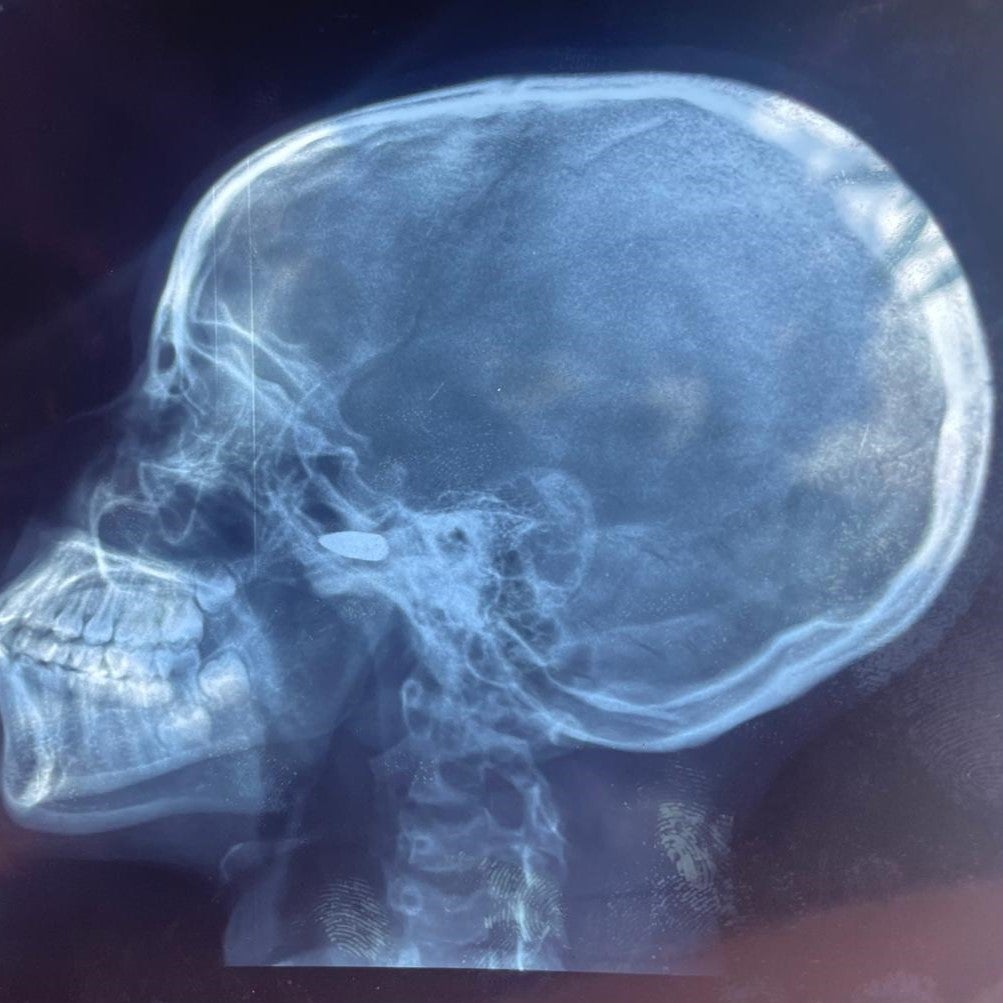

Das Röntgenbild eines 15-jährigen Mädchens, das am 9. Mai 2024 in Bébédja im Süden des Tschad von einem Querschläger in den Kopf getroffen wurde, nachdem die vorläufigen Ergebnisse der Präsidentschaftswahlen im Tschad bekannt gegeben worden waren.

© 2024 Private